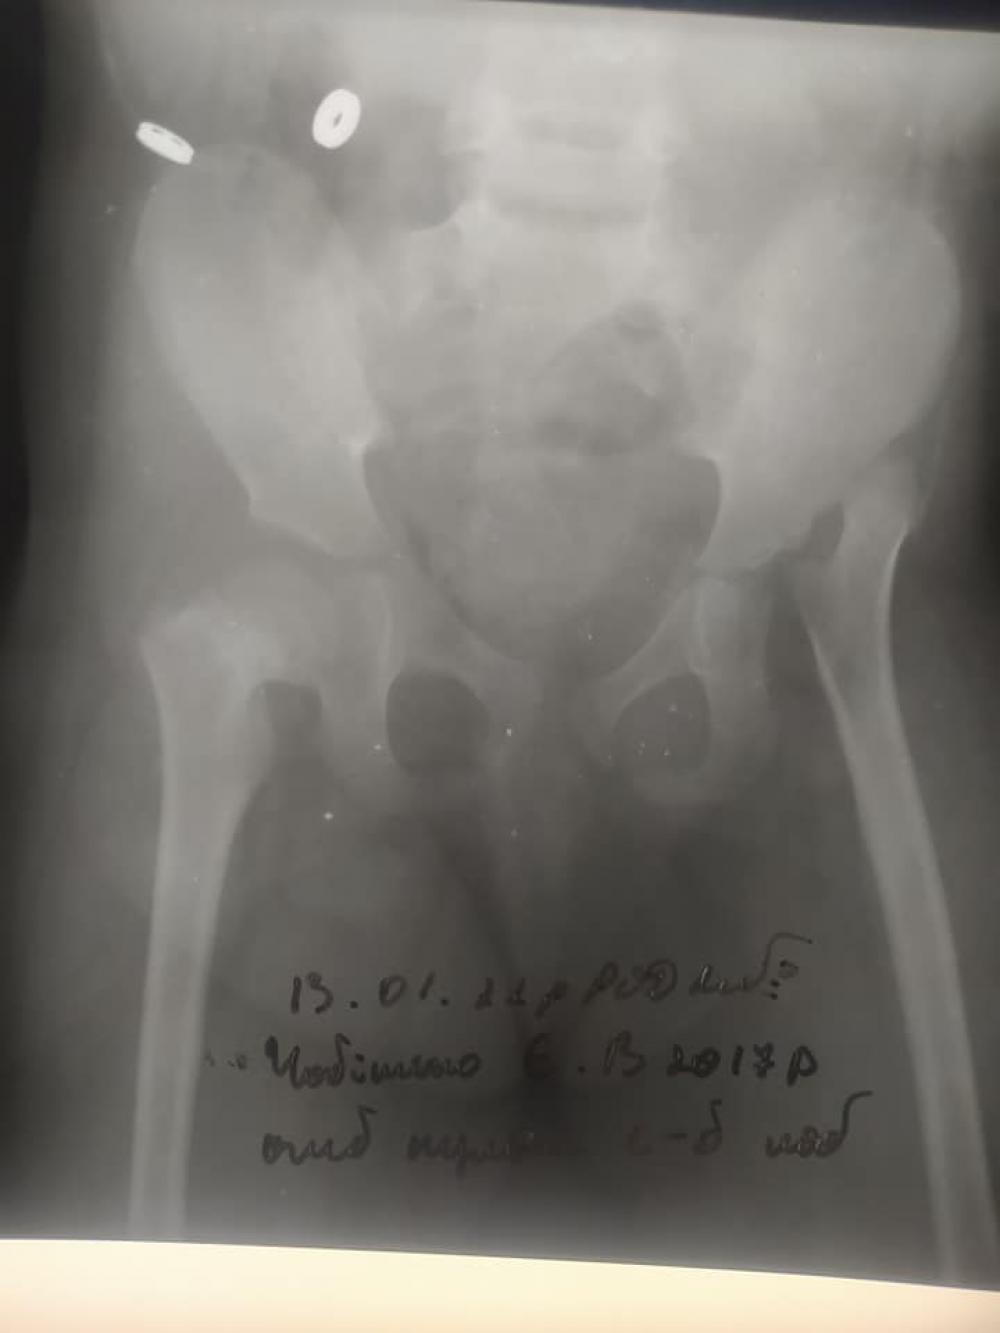

Після чергових консультацій з ортопедами постало питання термінового втручання в кульшовий суглоб для виправленню вивиху стегнової кістки, так як подальша вертикалізація дитини призведе до повного знищення елементів суглобу та викривлення спини в майбутньому. В Україні, на жаль, такі операції роблять з дуже тривалим подальшим гіпсуванням, яке може знівечити всі наші напрацювання за ці роки. Вартість операції значна і однакова що в нас, що закордоном, але методика лікування в Польщі відрізняється тим, що в подальшому це гіпсування буде в два рази меншим по терміну. Разом будуть прооперовані і стопи Єви, так звана ахілопластика. Без цієї операції Єву не можна активно реабілітовувати, а вона дуже активна дівчинка і хоче вже ставати на ніжки та ходити.